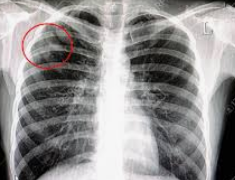

- 흉부 X-선 검사: 폐 내부의 결핵 병변을 확인하는 데 사용됩니다.

- 흉부 CT 검사: 필요시, 보다 정밀한 검사를 위해 시행됩니다.

- 정기적인 검사: 치료 중에는 정기적으로 객담 검사와 흉부 X-선 검사를 통해 치료 효과를 모니터링합니다.